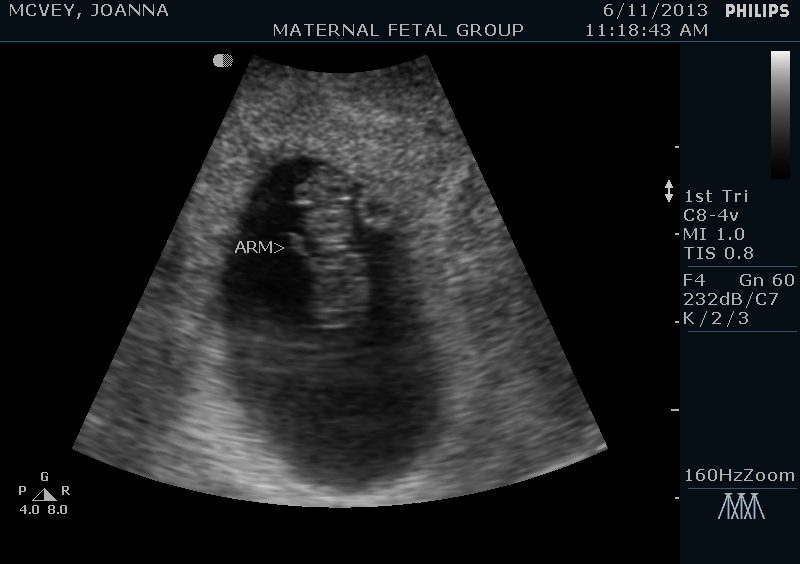

This baby is due January 21st, and we’ve already had our first doctor’s appointment and seen our little peanut via ultrasound.  At first I was positive this baby would be another boy, but since I’ve been SO sick this time around (much more than I was with Grayson), now I’m wondering if this one is a girl.  I guess only time will tell!

Here’s a couple pictures of our little munchkin.